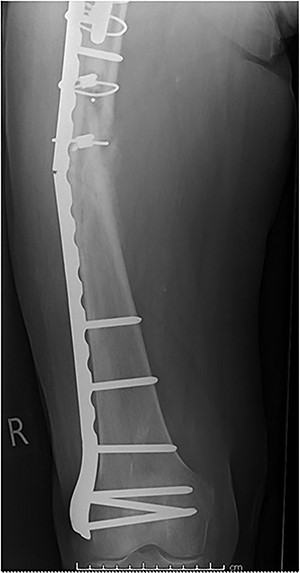

Case 2 (Figs 3–5): here difficulties were clearly encountered in achieving satisfactory reduction in the coronal plane. The screw immediately proximal to the fracture line is too close to the fracture.

Selecting a longer plate would have allowed proximal screws to sit more appropriately in order to reduce the risk of plate fatigue.

Case 3 (Figs 6 and 7): another case of fatigue fracture of the plate prior to bony union. Here cerclage wires close to the fracture site may have had the same effect as placing screws immediately adjacent to the fracture. It would seem reasonable to speculate that their exclusion may have led to a more satisfactory outcome.

Case 4 (Figs 8–10): once again, screw placement too close to the fracture site has resulted in internal plate stresses exceeding its load-bearing capacity.

Inter-fragmentary screws have been utilized here. This lady may have benefited from placing an anterior bridging plate at the time of her original procedure if it was not possible to avoid this screw configuration.